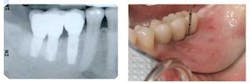

Mucositis (gingival inflammation, probing depth, bleeding on probing, no bone loss)

Peri-implantitis (probing depth and bone loss)Author bioStuart J. Froum, DDS, whose private practice is limited to periodontics and implant dentistry in New York City. Dr. Froum, a diplomate of the American Board of Periodontology, is currently a clinical professor in the Department of Periodontology and Implant Dentistry at the New York University Krieser Dental Center, as well as the director of clinical research in the Department of Periodontology and Implant Dentistry at the New York University Dental Center. He is the past president of the Northeast Society of Periodontics and is on both the Research Committee and the Continuing Education Oversight Committee of the Academy of Osseointegration. Dr. Froum is a trustee of the American Academy of Periodontology and the recipient of several awards: Hirschfeld Award from the Society of Periodontologists, the Clinical Research Award for 2004 and 2005, and the William J. Gies Award for 2006. You may contact Dr. Froum by email at [email protected].